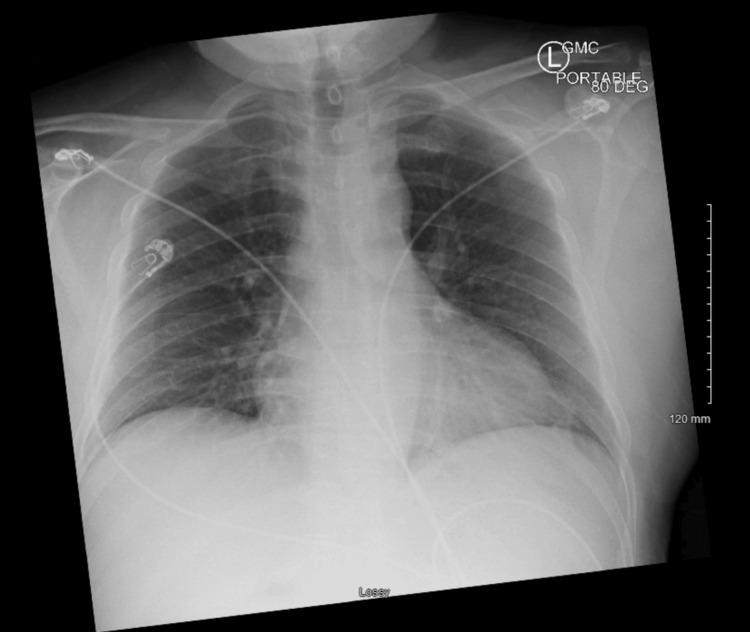

Kounis syndrome (KS) is an underrecognized and critical condition of acute coronary syndrome (ACS) triggered by an allergic reaction, via histamine-mediated coronary vasospasm and plaque disruption. We present a case of type 1 KS in a 42-year-old male patient who developed ST elevation myocardial infarction following an allergic reaction to epinephrine, diphenhydramine, and cocaine. Initially stable, he later experienced worsening chest pain with a significant rise in troponin. Coronary angiography with intravascular ultrasound (IVUS) imaging revealed a layered left anterior descending (LAD) thrombus with possible acute plaque rupture but no significant coronary artery disease (CAD) otherwise, which was successfully managed with medical therapy. This case underscores the importance of early recognition, cardiology involvement, and balancing treatment geared toward allergic and cardiac manifestations. This report aims to raise awareness of KS, and its documented exposures are essential for timely diagnosis, targeted management, and improved patient outcomes, as there would be more focus on treating the allergic reaction in these cases, which might be overlooked if ACS was to be attributed to CAD as the reason.

库尼斯综合征(KS)是一种由过敏反应引发的急性冠状动脉综合征(ACS),常因组胺介导的冠状动脉痉挛和斑块破裂而未被充分认识且病情危急。我们报告一例1型KS病例,患者为42岁男性,在对肾上腺素、苯海拉明和可卡因发生过敏反应后出现ST段抬高型心肌梗死。起初病情稳定,随后他胸痛加重,肌钙蛋白显著升高。冠状动脉造影及血管内超声(IVUS)成像显示左前降支(LAD)有分层血栓,可能存在急性斑块破裂,但无其他明显冠状动脉疾病(CAD),通过药物治疗成功处理。该病例强调了早期识别、心脏病学介入以及平衡针对过敏和心脏表现的治疗的重要性。本报告旨在提高对KS的认识,其记录的暴露情况对于及时诊断、针对性管理和改善患者预后至关重要,因为在这些病例中更多地关注治疗过敏反应,若将ACS归因于CAD作为原因,可能会忽略这一点。